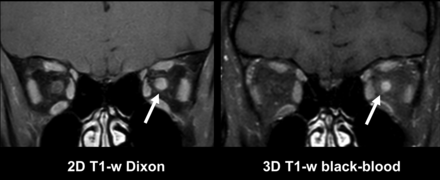

MR imaging of a 34-year-old female patient with symptoms of acute optic neuritis of the left eye with loss of vision and pain during eye movement for 3 days. Images of a contrast-enhanced 2D T1-weighted Dixon sequence with coronal orientation (left) and a contrast-enhanced 3D T1-weighted BB sequence with coronal reconstruction (right) are shown. Note a contrast-enhancing lesion in the left optic nerve in the intraorbital section with similarly high contrast in both sequences (arrows).